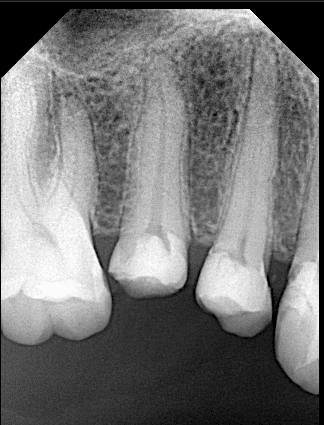

Pre-operative x ray

After DME

Cone fitt

After obturation

After preparation

Final x ray